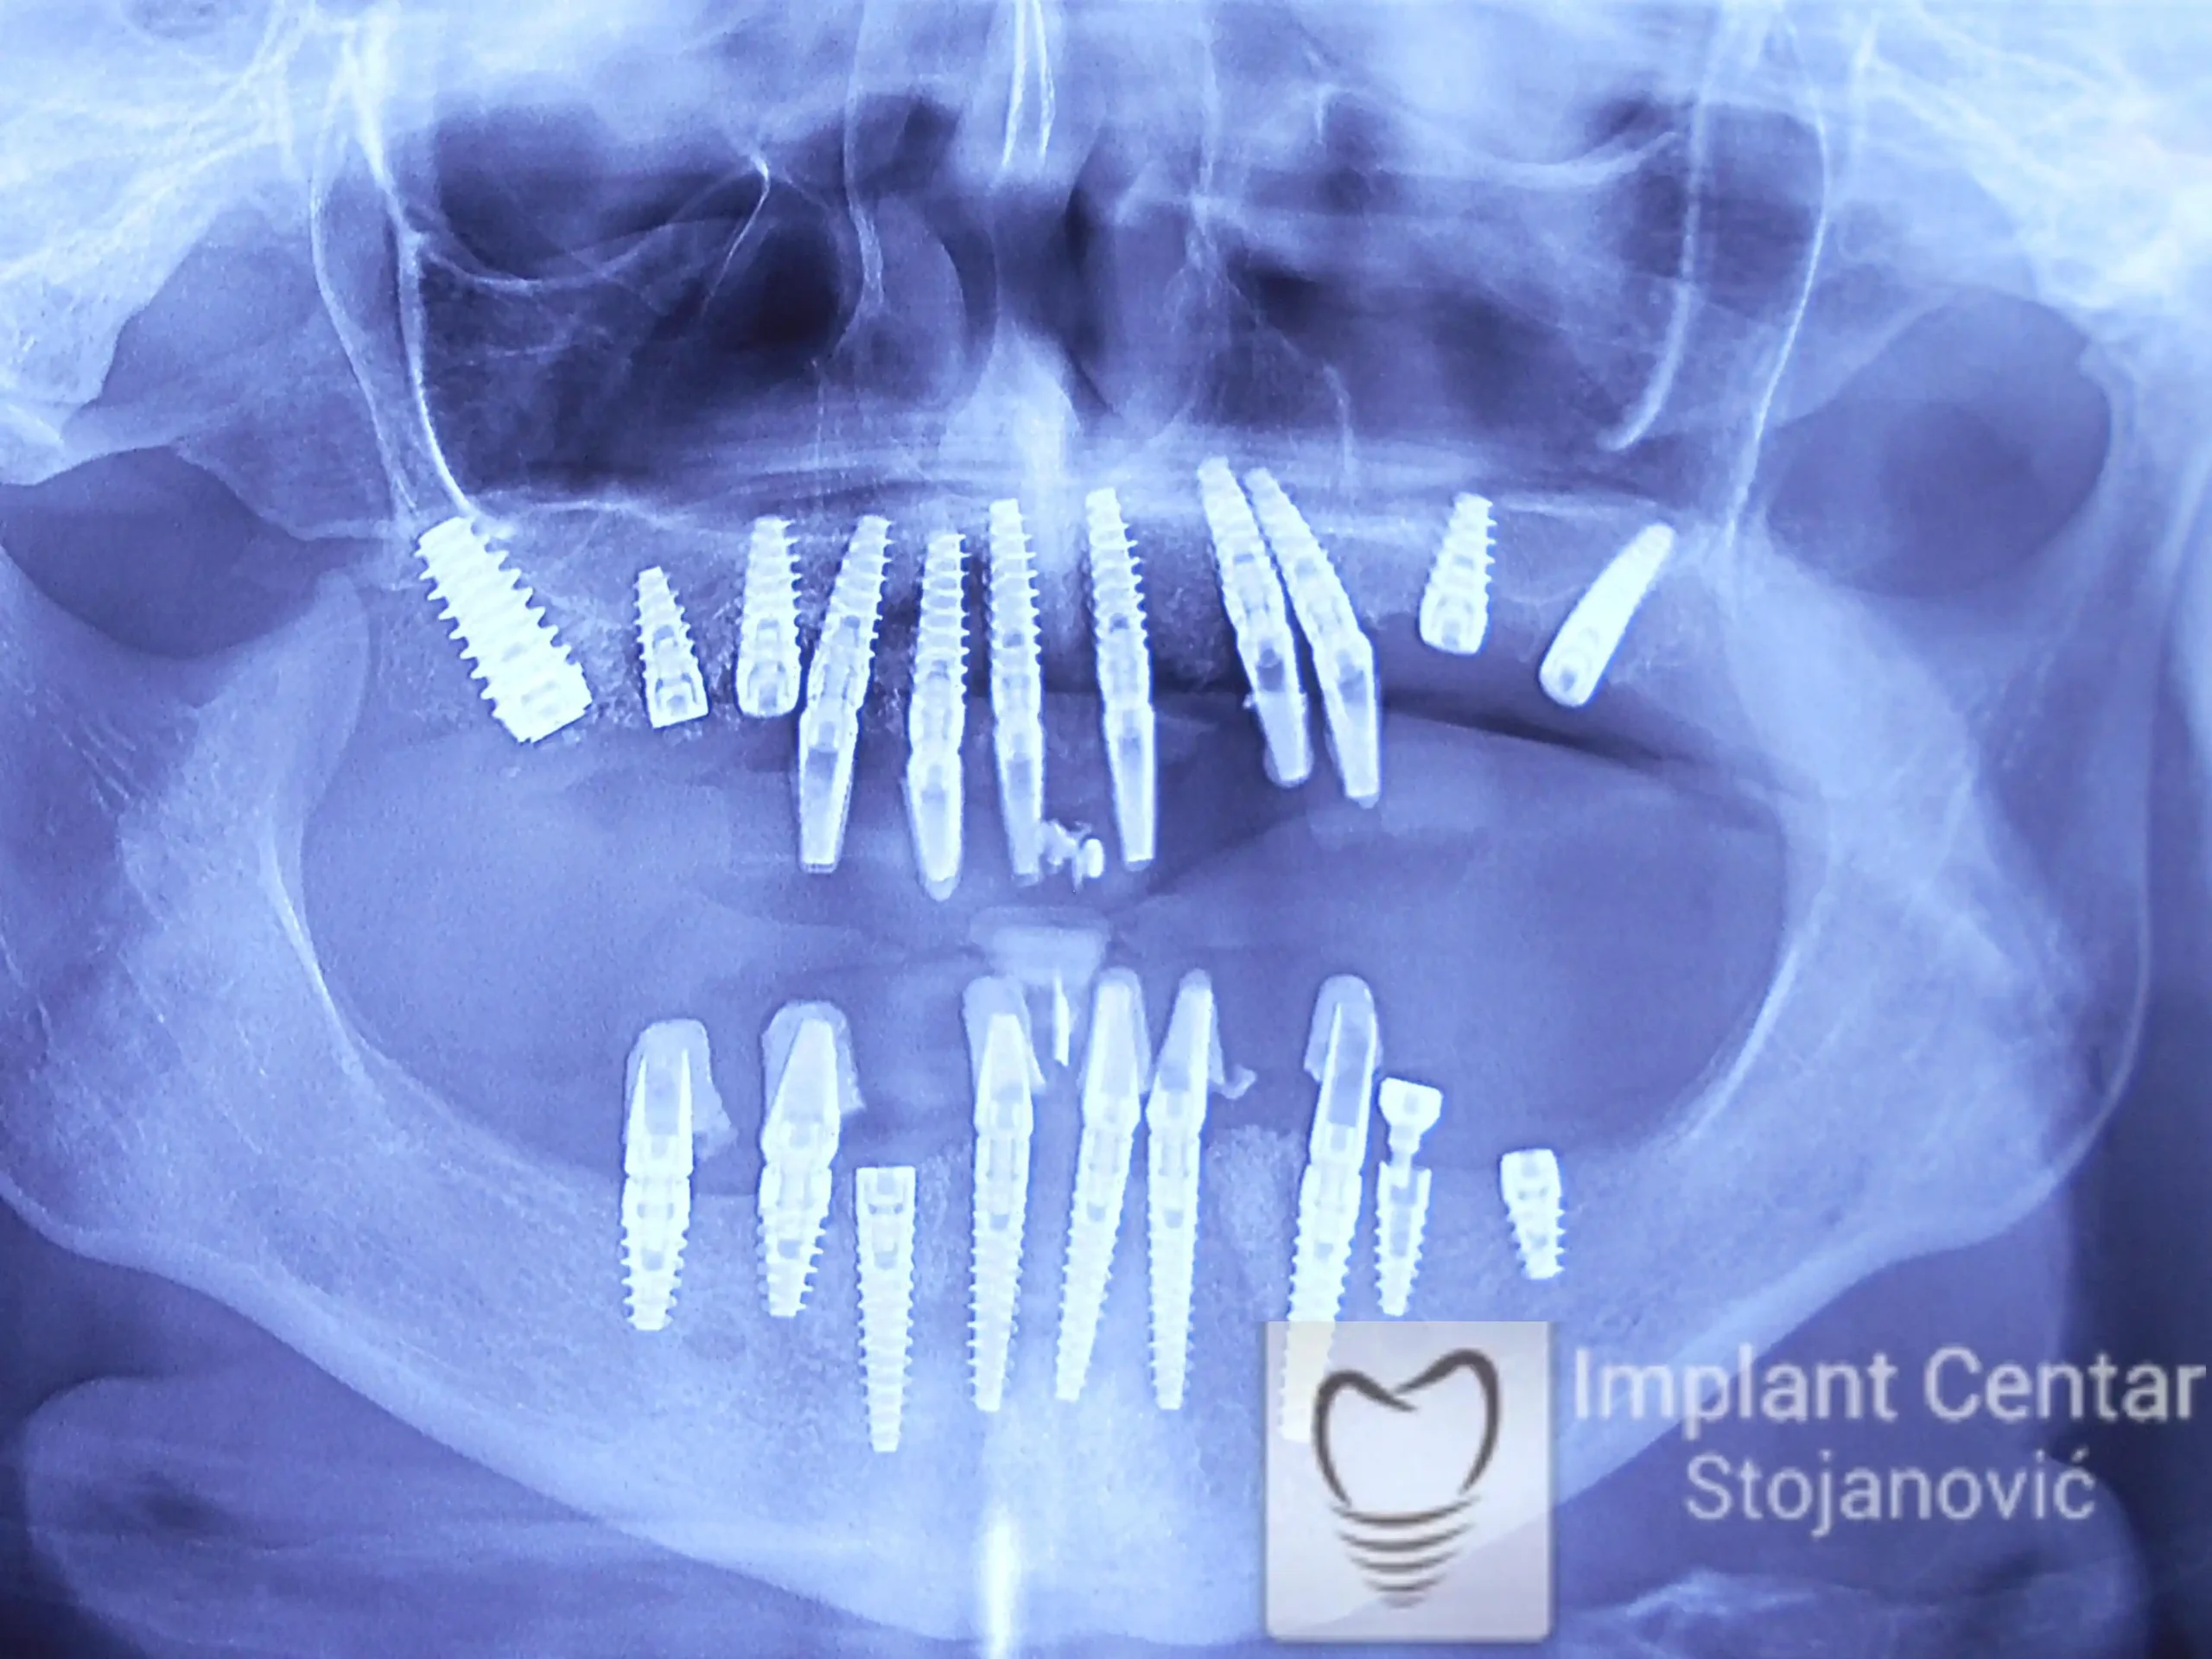

Na slici 1. slici 2. vidi se početno stanje — pacijent je imao prirodne zube, ali samo izradom novih mostova nije bilo moguće postići normalan odnos gornjih i donjih zuba (eugnatan zagrižaj).

Zbog toga je plan terapije uključivao vađenje svih preostalih zuba i ugradnju implantata u gornjoj i donjoj vilici. U gornjoj vilici postavljena su i dva tuberopterigoidna implantata, kao zamena za sinus lift proceduru, što se može videti na ortopan snimku nurađenom odmah nakon ugradnje (slika 3).